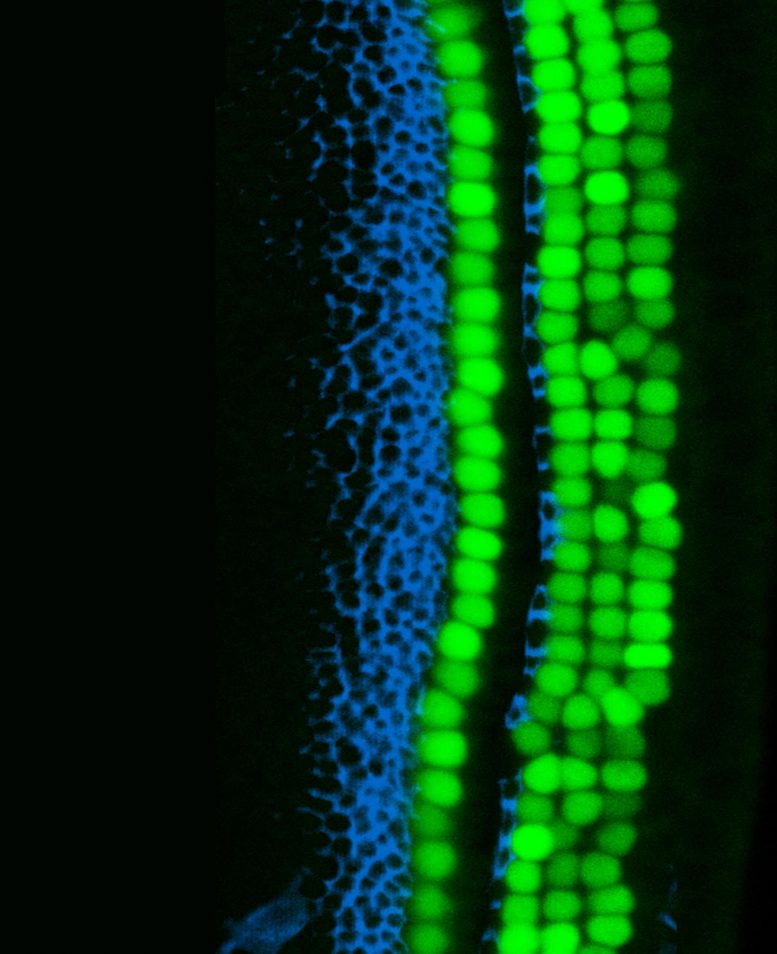

Corti 器官是内耳的听觉器官,包含成排的感觉听觉细胞(绿色),周围环绕着支持细胞(蓝色)。图片来源:Yassan Abdolazimi/Segil Lab/USC Stem Cell

在内耳中,听觉器官,即耳蜗,包含两种主要类型的感觉细胞:“毛细胞”,它们具有接收声音振动的毛发状细胞突起;以及发挥重要结构和功能作用的所谓“支持细胞”。